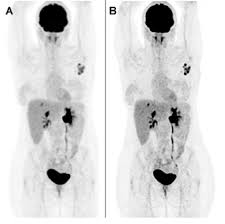

Controversies And Practices In Breast Cancer Screening Healthcare In Europe Com from healthcare-in-europe.com Bone scans, positron emission tomography (pet), and computed tomography (ct) all continue to be employed alone or in combination for the detection of breast cancers suspected to have spread. Ct scans can show a tumor's shape, size, and location. For example, it could be scar tissue left over from cancer killed off by. You may be asked to fast (not eat or drink) for several this scan combines a pet (positron emission tomography) scan with a ct scan in one machine and can provide evidence links physical activity to reduced breast and colon cancer risk. A ct scan can show whether breast cancer has spread to the lungs or liver. Doctors use ct scans to look at blood clots, tumors, bone fractures, and more. Ct scans are usually done at a hospital or radiology clinic. A radiographer operates the scanner.